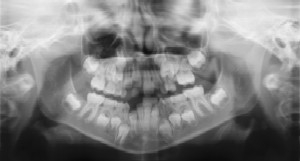

Dental Radiographs (X-Rays)

Radiographs (X-Rays) are a vital and necessary part of your child's dental diagnostic process. Without them, certain dental conditions can and will be missed.

Radiographs detect much more than cavities. For example, radiographs may be needed to survey erupting teeth, diagnose bone diseases, evaluate the results of an injury, or plan orthodontic treatment. Radiographs allow dentists to diagnose and treat health conditions that cannot be detected during a clinical examination. If dental problems are found and treated early, dental care is more comfortable for your child and more affordable for you.

The American Academy of Pediatric Dentistry recommends radiographs and examinations every six months for children with a high risk of tooth decay. On average, most pediatric dentists request radiographs approximately once a year. Approximately every 3 years, it is a good idea to obtain a complete set of radiographs, either a panoramic and bitewings or periapicals and bitewings.

Pediatric dentists are particularly careful to minimize the exposure of their patients to radiation. With contemporary safeguards, the amount of radiation received in a dental X-ray examination is extremely small. The risk is negligible. In fact, the dental radiographs represent a far smaller risk than an undetected and untreated dental problem. Lead body aprons and shields will protect your child. Today's equipment filters out unnecessary x-rays and restricts the x-ray beam to the area of interest. High-speed film and proper shielding assure that your child receives a minimal amount of radiation exposure.